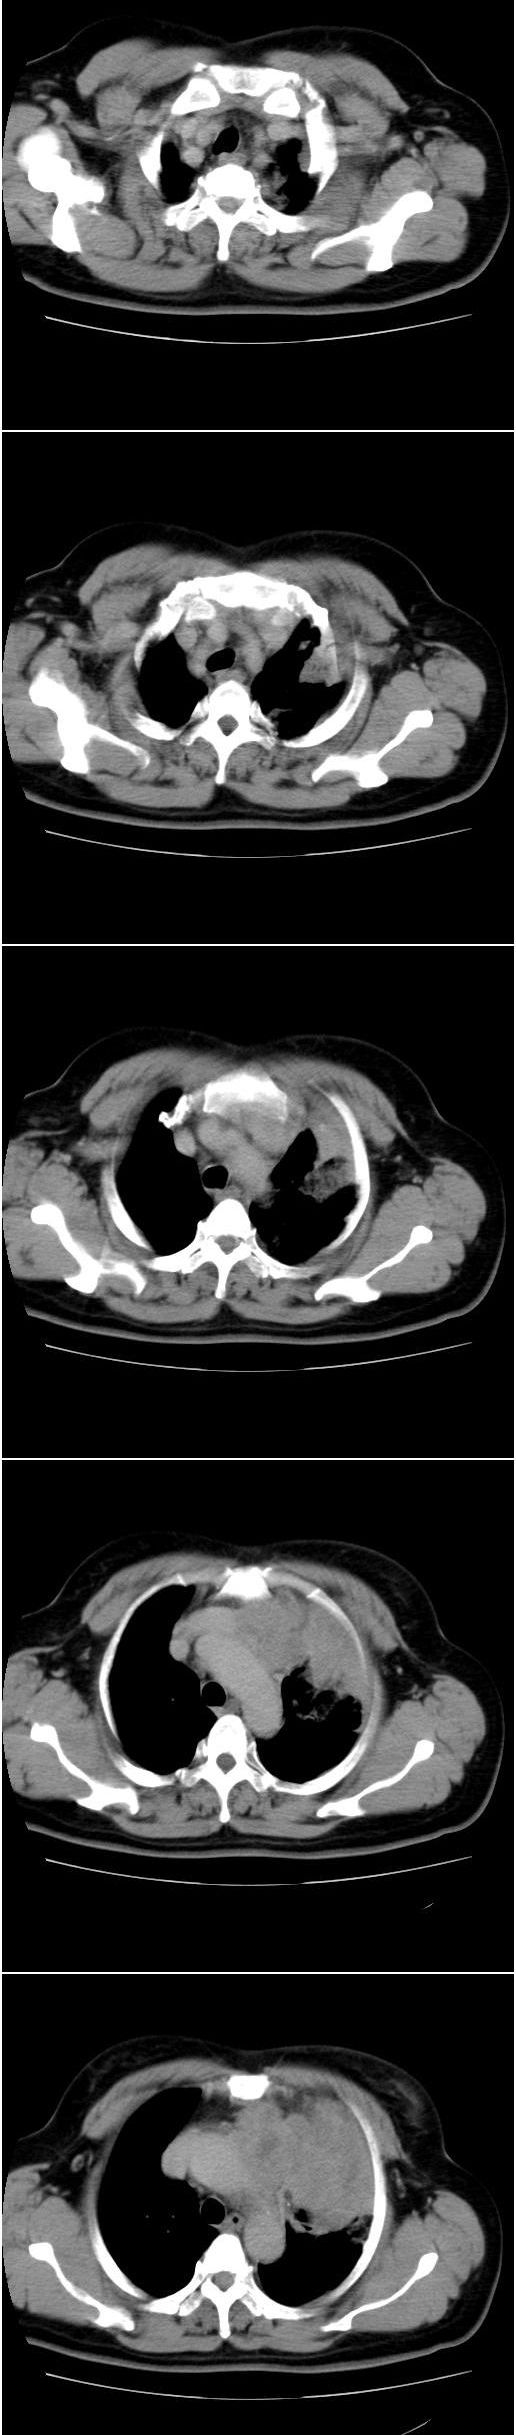

标题: CT13028:女,56岁。咳嗽、气促一月,咳血一周。CT值增加约30 [打印本页]

标题: CT13028:女,56岁。咳嗽、气促一月,咳血一周。CT值增加约30

左上肺肿块伴阻塞性改变,考虑肺癌可能大

感觉病灶主要来源于前上纵隔,向周围浸润,考虑为侵袭性胸腺瘤。

考虑左上肺癌(周围型)伴左肺门及纵隔转移(主肺动脉窗旁病灶可能为肿大并坏死的淋巴结),不除外纵隔型肺癌

软组织肿块,应该有肺不张(因为左膈及脾脏\\胃抬高明显):考虑中央ca

支持纵隔旁型肺癌伴主动脉弓\\主肺动脉及左侧头壁动脉受侵.

考虑左肺中心性肺癌并纵隔淋巴结转移,累及左肺动脉及左侧头臂静脉.但不除外纵隔恶性肿瘤累及肺组织.

考虑左肺中心性肺癌并纵隔淋巴结转移,纵隔恶性肿瘤累及肺组织的可能性小,因为后者一般不会导致横膈上抬。

考虑左侧中央型肺癌伴左肺上叶肺不张及前纵隔淋巴转移。

1)考虑为:左肺上叶中心型肺癌伴左肺上叶阻塞性肺炎、节段性肺不张,左肺门及纵隔淋巴结转移。2)左侧少量胸腔积液。